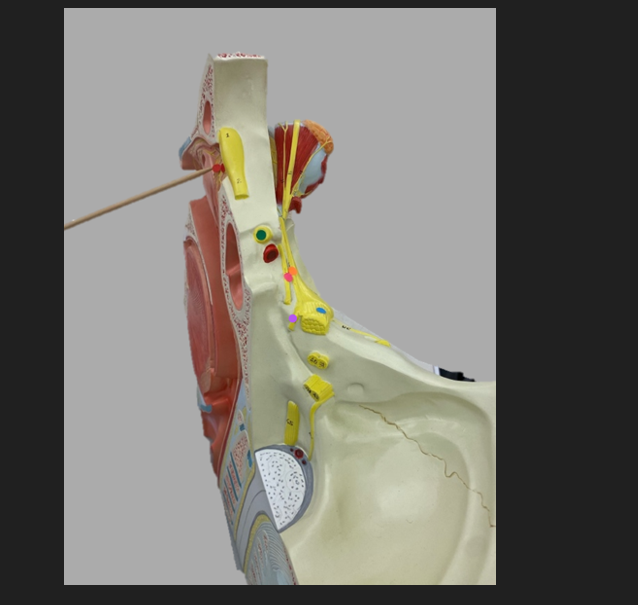

green dot

spinal nerve

orange dot

ventral root

pink dot

dorsal root

blue dot

dorsal root ganglion

red dot

dorsal ramus

yellow dot

ventral ramus

purple dot

anterior median fissure

red dot

posterior (dorsal) horn

purple dot

lateral horn

dark blue dot

anterior (ventral) horn

orange dot

dorsal column

yellow dot

lateral column

dark green

anterior column

line green and pink doit

gray commissure

light blue dot

posterior median sulcus